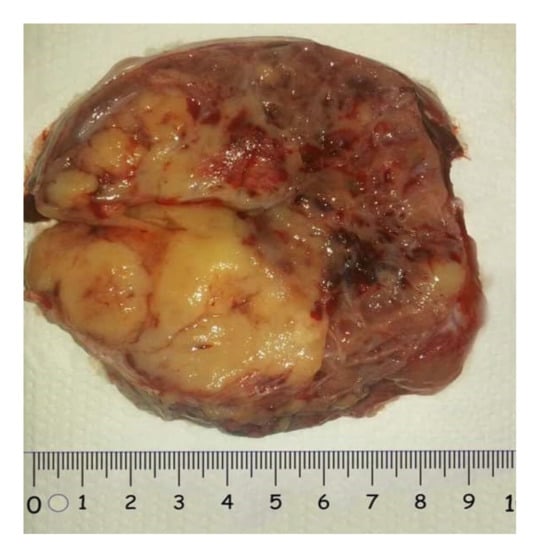

2.2. Mature Cystic Teratoma

2.2.2. Macroscopic Appearance